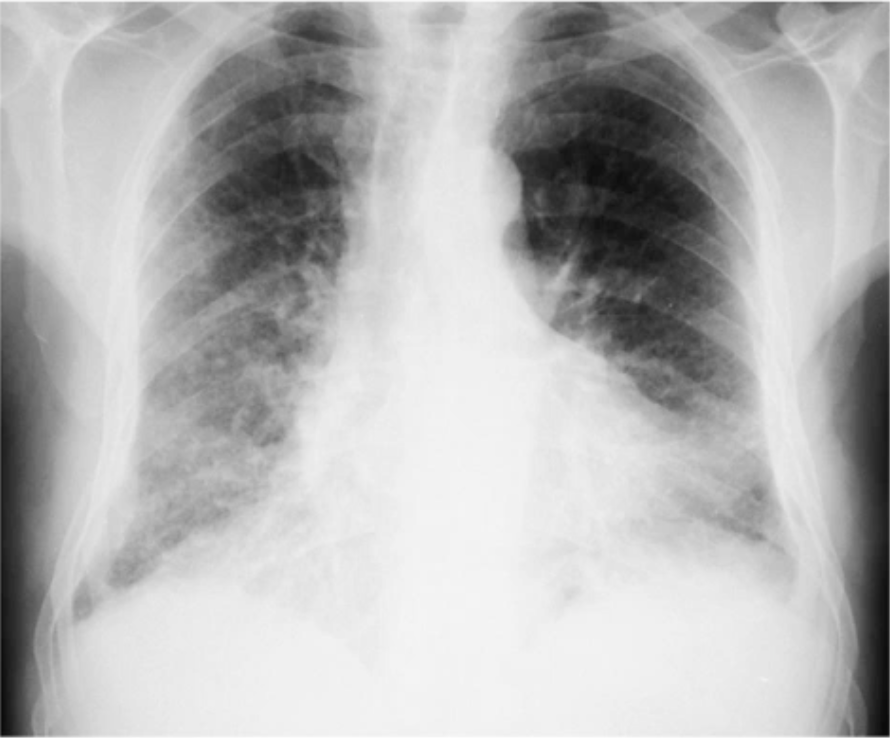

What is seen on this CXR?

Pulmonary Fibrosis

Reticular nodular shadowing (lines and dots)